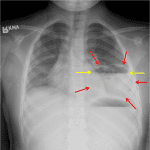

Age: 5

Sex: Female

Indication: Fever, shortness of breath

Sample ReportLeft lower lobe rounded opacification with an air-fluid level, which is concerning for a lung abscess.

Small left pleural effusion.

Additional segmental right perihilar airspace opacities likely represent atelectasis.